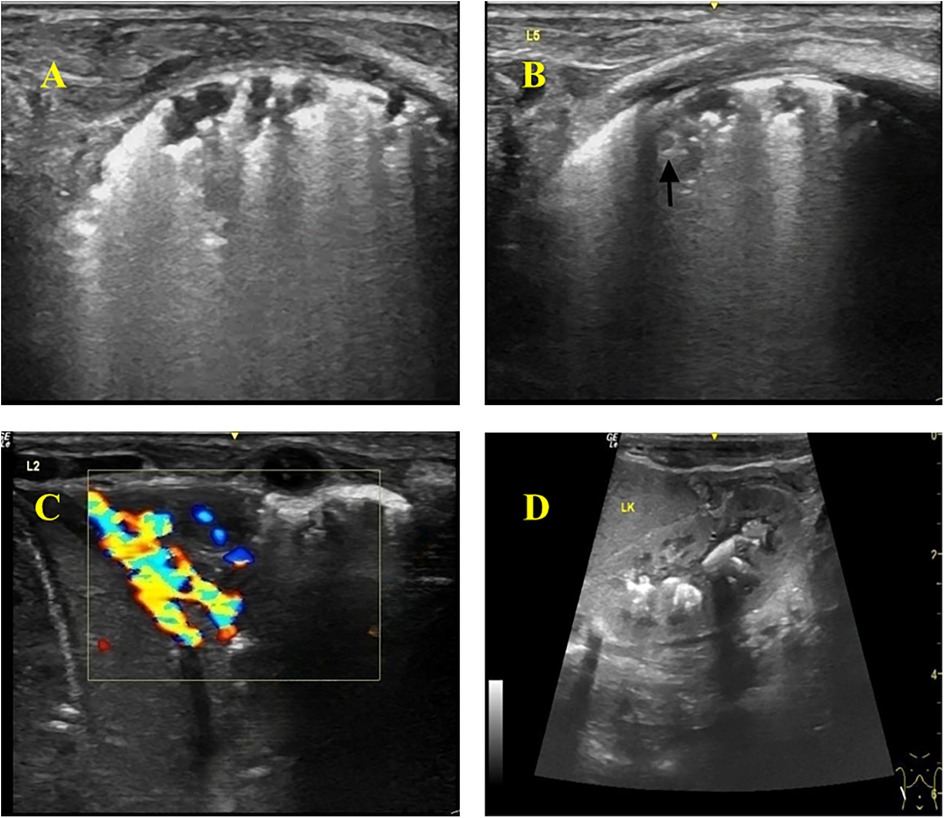

Thickened, irregular pleura with “shred sign” (hyperechoic fragments). Subpleural consolidations with heterogeneous echotexture and vascularity. Multiple solid lesions of varying sizes were visible in the subpleural areas of both lungs, with the larger ones mainly located in the lung apices and bases, involving 2–3 intercostal spaces. The pleura was thickened at the sites of consolidation, with a thickness of about 2 mm. Blood flow signals were detected in the consolidated areas, with a resistance index (RI) of 0.86–0.88. Hepatosplenomegaly and renal calcifications were also identified on abdominal ultrasound (Figure 2).

Four-panel ultrasound images labeled A, B, C, and D. Panel A shows a homogeneous pattern typical of healthy tissue. Panel B includes an arrow indicating an area of interest, possibly an anomaly. Panel C features color Doppler imaging, displaying blood flow with blue and red areas. Panel D presents a standard grayscale ultrasound view of an organ, labeled \

Figure 2. Color Doppler ultrasonography of the infant. (A) Thickened and hyperechoic pleural lines in both lungs, with partial discontinuity. (B) Multiple discontinuous small subpleural hypoechoic lesions (ragged cloth sign) with scattered hyperechoic patchy areas (fragmentation sign) at the margins. Nodular changes within some consolidated areas. (C) Wedge-shaped consolidation in the lower lobes of both lungs, with heterogeneous echogenicity and small hypoechoic areas, showing rich blood flow signals on Doppler. (D) Abdomen (Color Doppler Ultrasound): Hepatomegaly and splenomegaly. Calcifications visible in the renal pelvises and calyces of both kidneys.

In this case, the infant presented with recurrent fever and poor response to antibiotics. Chest x-ray showed prominent lung markings, prompting a lung color Doppler ultrasound, which revealed: (1) Abnormal pleural line: appeared rough, irregular, and hyperechoic, with posterior confluent or dense B-lines, some discontinuous with thin pleural segments. (2) Multiple irregular consolidations: subpleural hypoechoic consolidations of varying sizes and shapes were observed. Smaller lesions were highly irregular with fragmented hyperechoic borders, while larger wedge-shaped consolidations were seen in the apical and lower lobes, also with fragmented hyperechoic edges. The consolidations showed minimal aeration, heterogeneous echogenicity (patchy hypoechoic areas), and grade 2 blood flow signal. (3) Nodular changes: Nodular lesions with slightly hyperechoic rims were detected within subpleural consolidations.

Abdominal color Doppler ultrasound revealed hepatosplenomegaly and multiple hyperechoic foci in the renal pelvis, but no enlarged mediastinal lymph nodes.